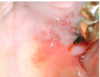

What is this radiographic & clinical findings?

Periapical cyst

shows inflammation at site

abscess developed fistula tract thru

soft tissue. Pt will have pain until

pressure is released